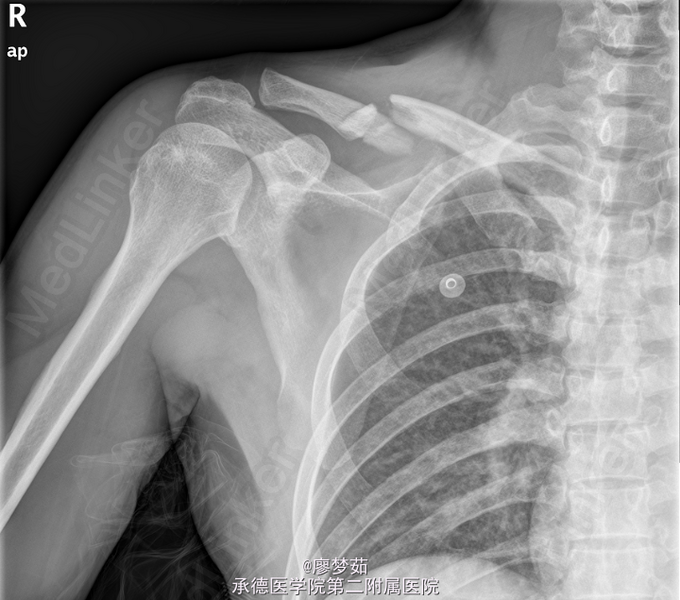

患者,男,40岁,因“ 重物压伤致全身多处疼痛12小时。 ”入院。 患者约12小时前不慎被约2吨重水泥包压伤致全身多处疼痛,以左胸部及右肩部为著.

胸廓挤压试验(+),右肩部肿胀,压痛(+). X线片示“右锁骨中外侧段粉碎性骨折。”